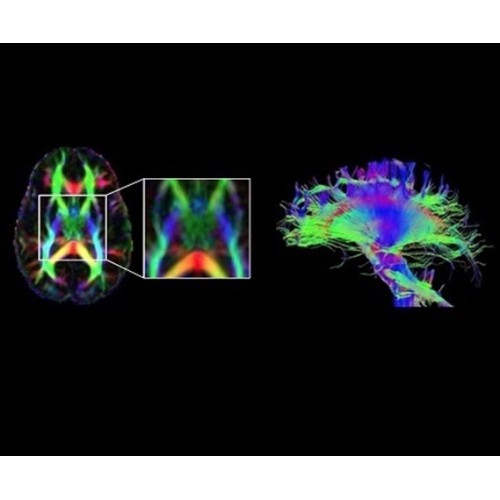

В систему SIGNA PET/MR встроены запатентованные детекторы кремниевого фотоумножителя (SiPM) и сверхчувствительные кристаллические сцинтилляторы на основе лютеция толщиной 25 мм. Благодаря этому обеспечивается исключительная чувствительность и возможность использования времяпролетной диагностики (TOF).

Кроме того, в результате использования технологии TOF и инновационной технологии реконструкции Q.Clear вы сможете добиться прекрасного соотношения сигнал/шум. А благодаря технологии нулевого времени эхо (ZTE) визуализировать костную структуру без ионизирующего излучения. Все эти разработки для улучшения качества сканирования и точности анализа помогут вам использовать весь потенциал ПЭТ/МРТ.

Новейшая платформа SIGNA Works4 повышает производительность ключевых технологий визуализации GE Healthcare. SIGNA Architect поставляется с предустановленными стандартными приложениями. Расширенные функции SIGNA Works с возможностью обновления позволят устанавливать новые приложения в соответствии с растущими потребностями вашей клинической практики.

Стандартный пакет приложений SIGNA Works позволит вам достичь желаемых результатов в клинической практике благодаря набору высокоэффективных средств визуализации. Программные приложения, входящие в состав данных клинических пакетов, включают широкий спектр контрастов, функции обработки 2D- и 3D-данных, а также возможность коррекции артефактов движения. SIGNA Works предоставляет набор инструментов, необходимых для проведения эффективного клинического исследования.

• Специальный пакет приложений для измерения и сравнения объемных изображений ЦНС с нормами поможет вам в диагностике нейродегенеративных заболеваний, а дополнительные инструменты визуализации — в постановке точного диагноза с помощью бета-амилоидов и радиоизотопных маркеров ФДГ.